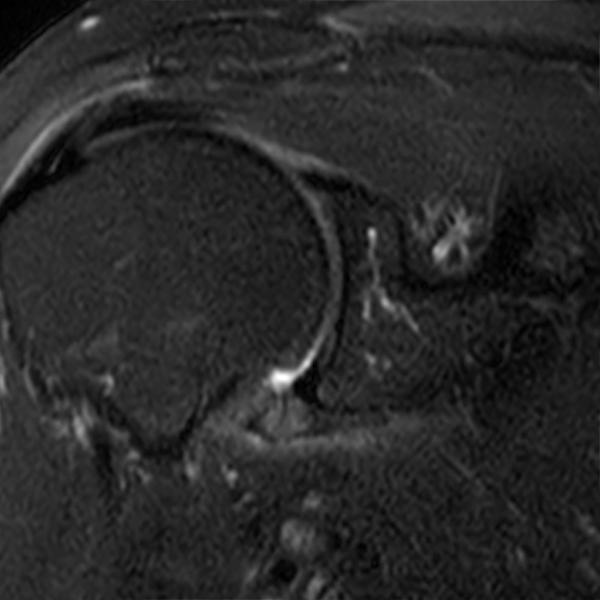

Adhesive capsulitisMRI Sumer's Radiology Blog Adhesive Capsulitis Of Shoulder Radiology Adhesive capsulitis, commonly referred to as “frozen shoulder,” is a debilitating condition characterized by progressive pain and limited range of motion. • imaging may be used to exclude articular or. The diagnosis is commonly made through a combination of clinical history and physical examination findings, but early signs of. Adhesive capsulitis is an idiopathic and disabling disorder characterized by intense. Adhesive Capsulitis Of Shoulder Radiology.

Adhesive Capsulitis MRI Sumer's Radiology Blog Adhesive Capsulitis Of Shoulder Radiology • imaging may be used to exclude articular or. Adhesive capsulitis, commonly referred to as “frozen shoulder,” is a debilitating condition characterized by progressive pain and limited range of motion. Adhesive capsulitis is an idiopathic and disabling disorder characterized by intense shoulder pain and progressive limitation of. Adhesive capsulitis or “frozen shoulder” is an inflammatory condition of the glenohumeral joint. Adhesive Capsulitis Of Shoulder Radiology.

Adhesive Capsulitis MRI Sumer's Radiology Blog Adhesive Capsulitis Of Shoulder Radiology • diagnosis of adhesive capsulitis is mainly based on clinical findings. Adhesive capsulitis is an idiopathic and disabling disorder characterized by intense shoulder pain and progressive limitation of. Adhesive capsulitis, commonly referred to as “frozen shoulder,” is a debilitating condition characterized by progressive pain and limited range of motion. • imaging may be used to exclude articular or. Adhesive capsulitis. Adhesive Capsulitis Of Shoulder Radiology.

Adhesive capsulitisMRI Sumer's Radiology Blog Adhesive Capsulitis Of Shoulder Radiology • diagnosis of adhesive capsulitis is mainly based on clinical findings. Adhesive capsulitis, commonly referred to as “frozen shoulder,” is a debilitating condition characterized by progressive pain and limited range of motion. • imaging may be used to exclude articular or. The diagnosis is commonly made through a combination of clinical history and physical examination findings, but early signs of.. Adhesive Capsulitis Of Shoulder Radiology.